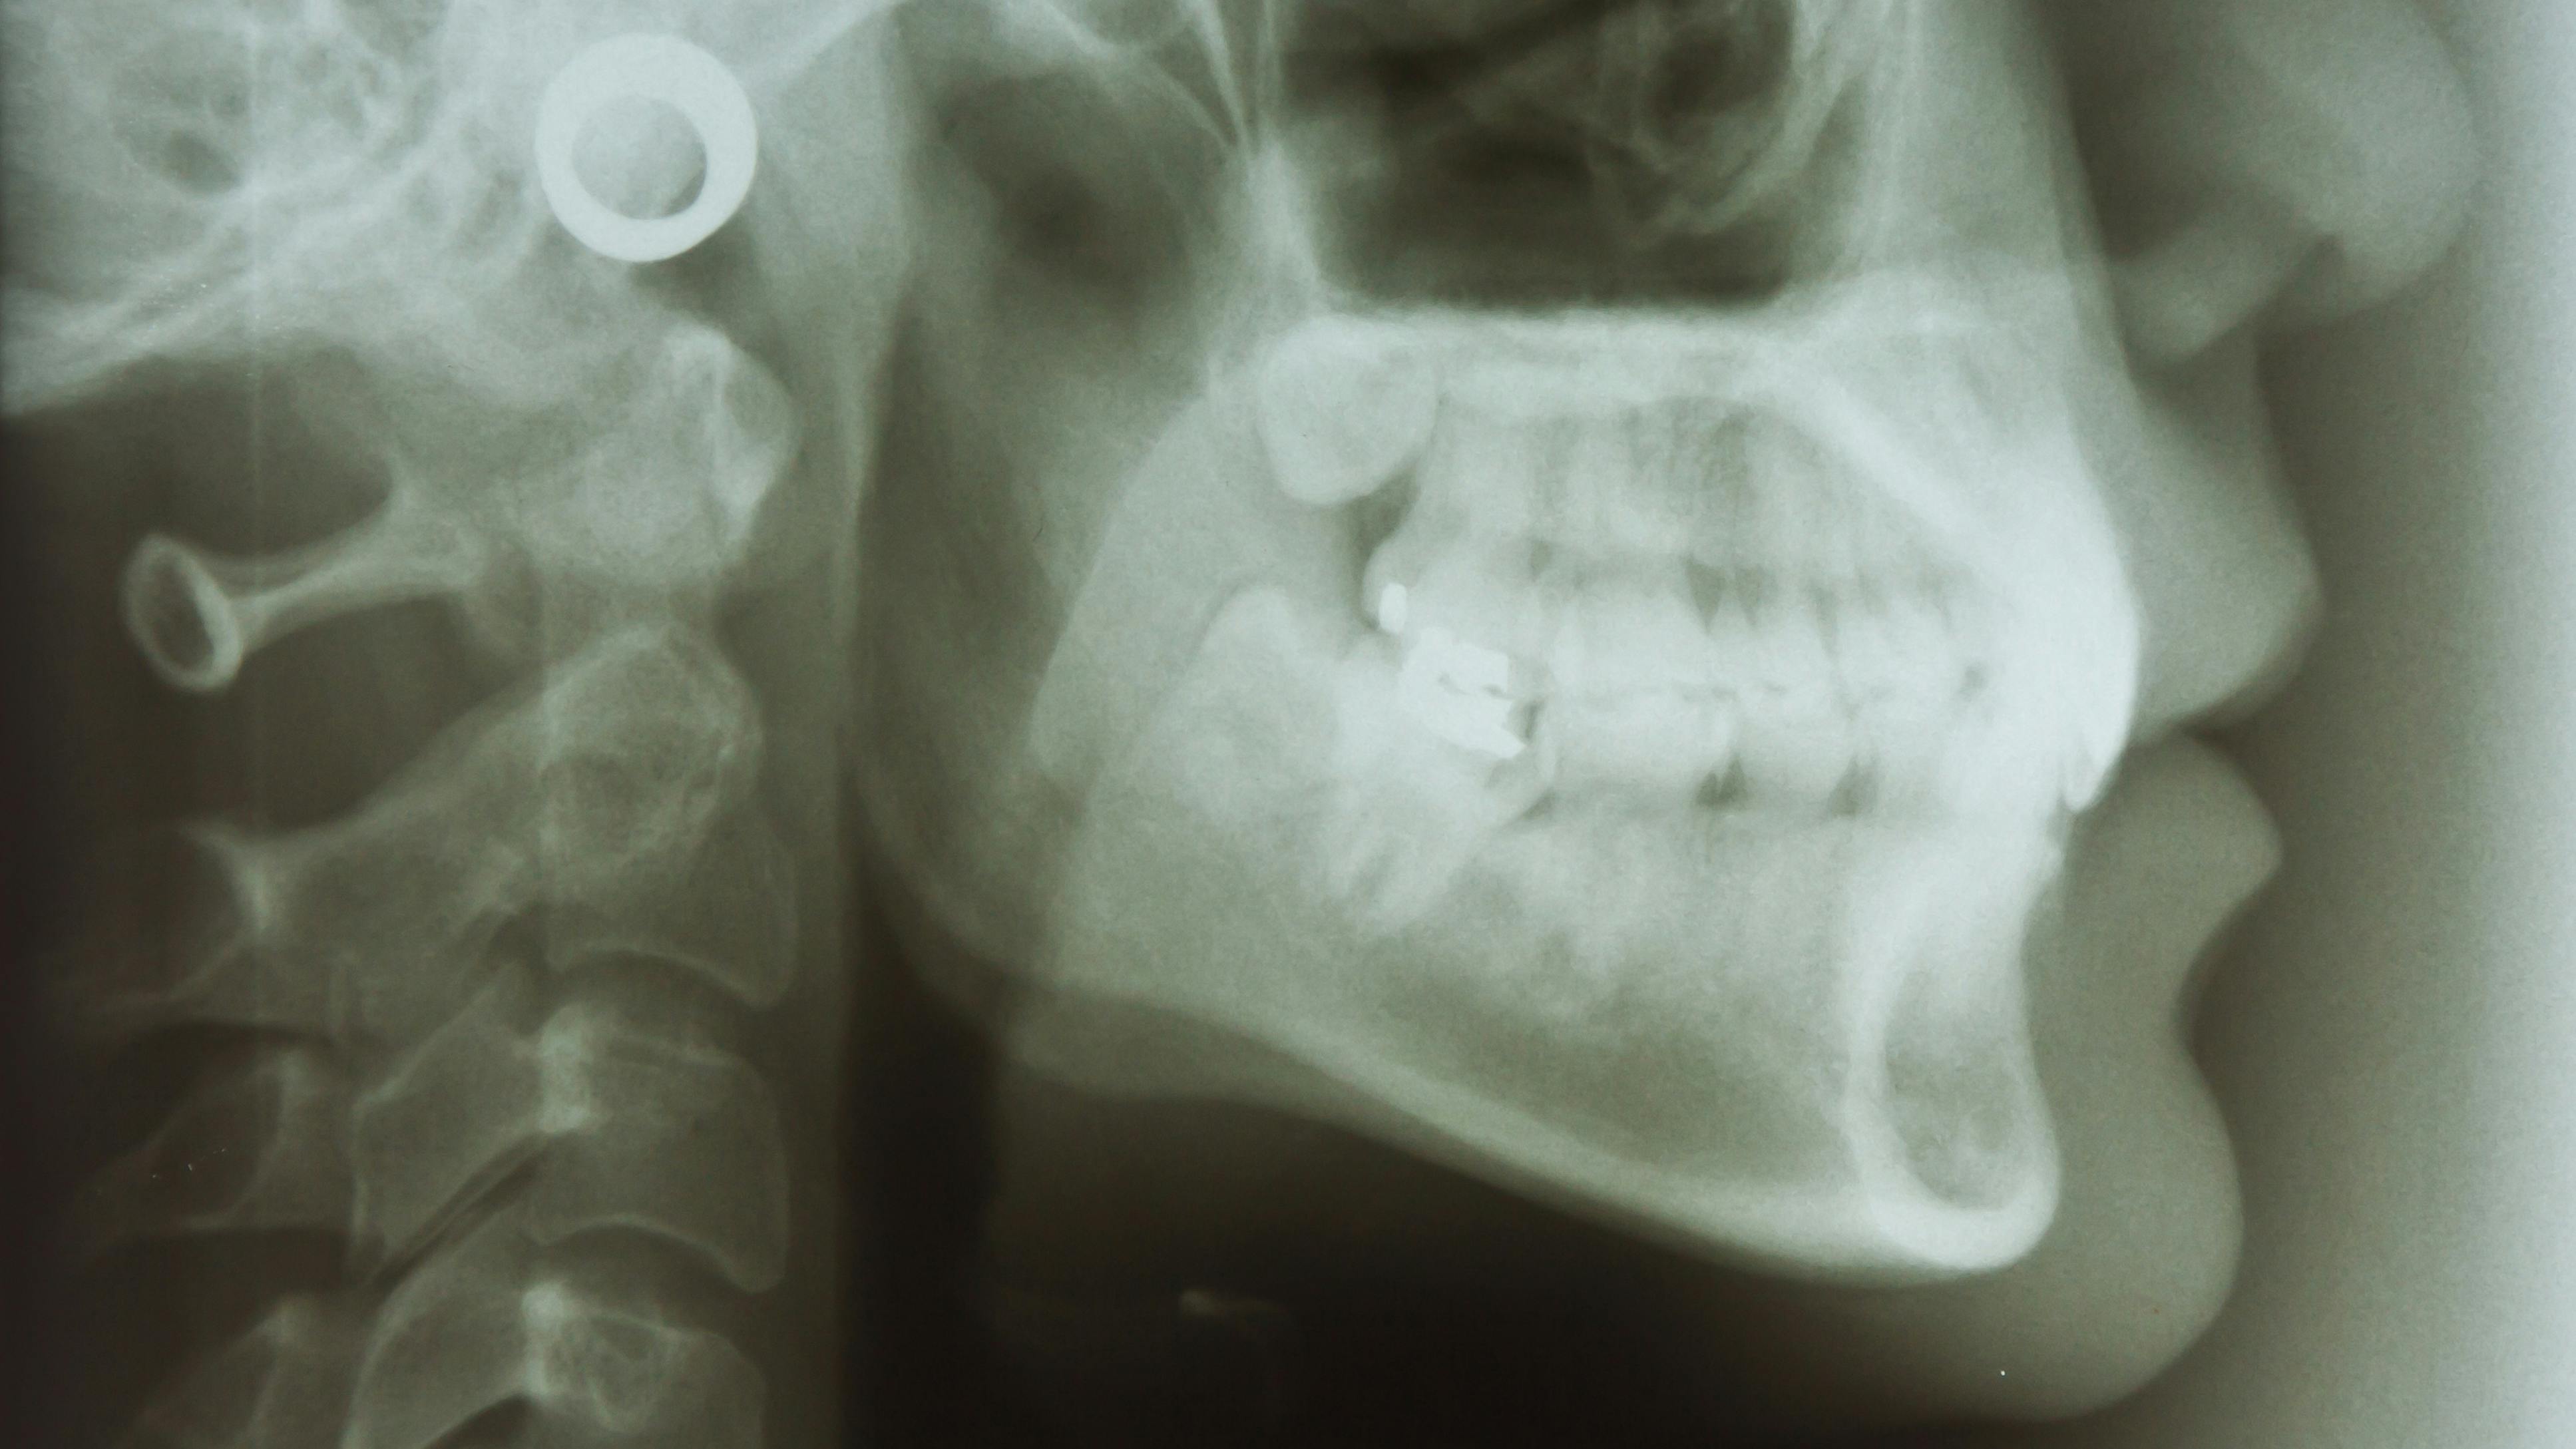

Extraoral exam: A large neck (generally greater than 16 inches), obesity, forward head posture, retrognathic skeletal profile, or the patient’s inability to easily seal their lips can be noteworthy.

Intraoral exam: A scalloped tongue, significant tongue-tie, enlarged tonsils, severe overjet and/or overbite, large tongue, or a class 3 or 4 Mallampati score can be reason for concern.